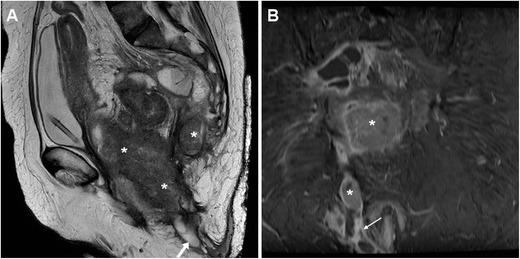

Enterocutaneous fistulas (ECFs) represent abnormal communications between the gastrointestinal tract and the skin. Nowadays, the majority (~80%) of ECFs develops secondary to abdominal surgeries; alternative, less common causes include chronic inflammatory bowel diseases (IBD) such as Crohn's disease, tumours, and radiation enteritis in descending order of frequency. These rare disorders require thorough patient assessment and multidisciplinary management to limit the associated morbidity and mortality. This pictorial review includes an overview of causes, clinical manifestations, complications and management of ECFs. Afterwards, the imaging appearances, differential diagnoses, and therapeutic options of post-surgical, IBD-related, and malignant ECFs are presented with case examples. Most of the emphasis is placed on the current pivotal role of CT and MRI, which comprehensively depict ECFs providing cross-sectional information on the underlying postsurgical, neoplastic, infectious, or inflammatory conditions. Radiographic fistulography remains a valid technique, which rapidly depicts the ECF anatomy and confirms communication with the bowel. The aim of this paper is to increase radiologists' familiarity with ECF imaging, thus allowing an appropriate choice between medical, interventional, or surgical treatment, ultimately resulting in higher likelihood of therapeutic success.

• Enterocutaneous fistulas may complicate abdominal surgery, sometimes Crohn's disease and tumours. • The high associated morbidity and mortality result from sepsis, malnutrition and metabolic imbalance. • The multidisciplinary management of ECFs requires thorough imaging for correct therapeutic choice. • Radiographic fistulography rapidly depicts fistulas and communicating bowel loops in real-time. • Multidetector CT and MRI provide cross-sectional information on fistulas and underlying diseases.